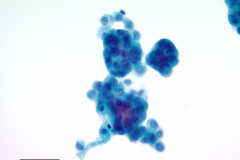

Cytology: Cytologic features suggestive of epithelioid hemangioendothelioma include spindle or polygonal epithelioid cells with moderate to abundant dense cytoplasm, well-defined cytoplasmic borders, and intracytoplasmic vacuoles and may present as single cells, small clusters or sheets. The large, eccentric nuclei are mildly pleomorphic with nuclear grooves, and nuclear cytoplasmic inclusions along with finely granular chromatin, irregular nuclear membranes, and nucleoli.4,5 Histologic features commonly seen in EHE include myxoid stroma, hyalinized stroma, and chondromyxoid stroma, as well as infrequent-to-frequent mitoses, erythrocytes, and a general absence of necrosis.3,4

This case reflects some of these features, including finely granular chromatin, enlarged, round nuclei, prominent nucleoli, dense and abundant cytoplasm, and formation of small groups. A fluid environment can also account for the cellular groupings seen in this case.

Adenocarcinoma is a top differential in this case because it was initially signed out as such based on cytological findings. Image 4 shows round cells grouped together with finely granular chromatin and nucleoli, and Image 5 has cells that form pseudo-rosettes and cells resembling signet-ring cells. Density of the cytoplasm should be taken into consideration when differentiating the two entities, however this criterion is not unique to epithelioid hemangioendothelioma. Immunohistochemistry stains to confirm adenocarcinoma are TTF-1 for lung primary, and CK7, CK20 or CEA for gastric signet ring adenocarcinoma.10 ERG stains positive in prostate adenocarcinoma and endothelial cells which could be useful in this case of a female patient. 9